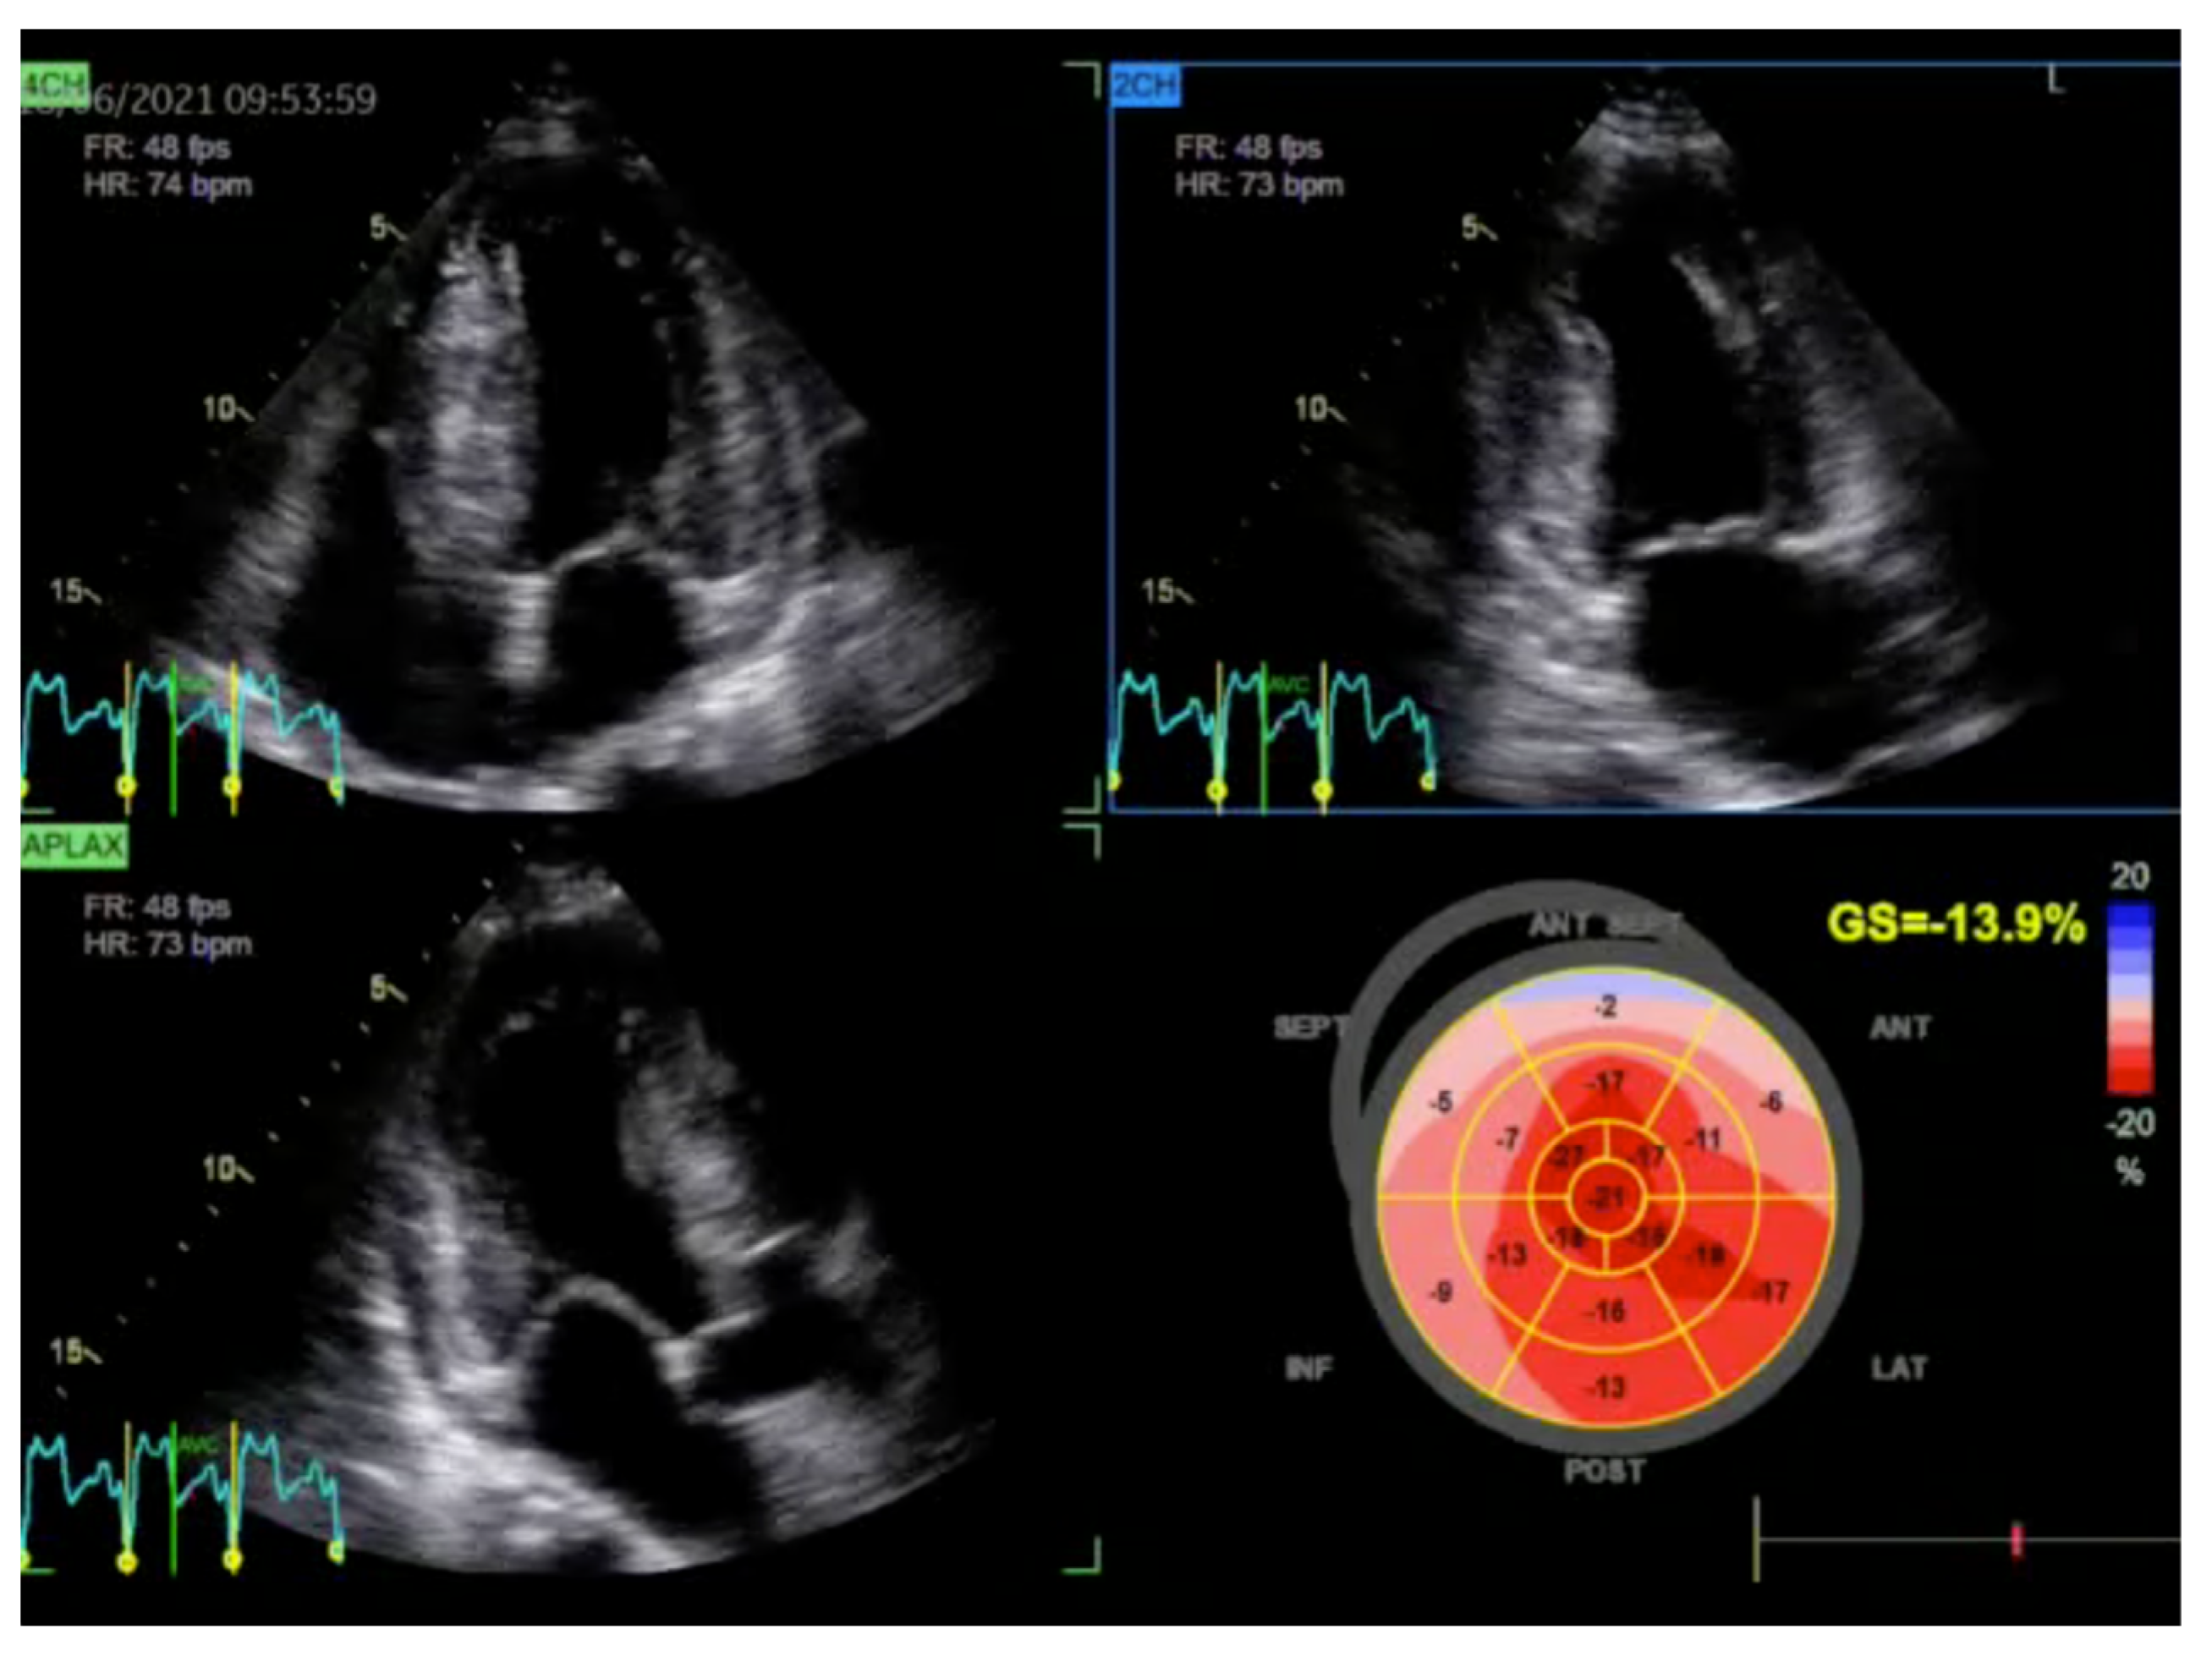

2.1. Echocardiography: The First Line of Diagnosis

- Gąsior, T.; Zaborska, B.; Stachowiak, P.; Sikora-Frąc, M.; Mizia-Stec, K.; Kasprzak, J.; Bodys, A.; Bijoch, J.; Szmagała, A.; Kosior, D.A.; et al. Echocardiographic Assessment of Left Ventricular Function in Three Oncologic Therapeutic Modalities in Women with Breast Cancer: The ONCO-ECHO Multicenter Study. J. Clin. Med. 2024, 13, 2543. [Google Scholar] [CrossRef]

- Gherbesi, E.; Gianstefani, S.; Angeli, F.; Ryabenko, K.; Bergamaschi, L.; Armillotta, M.; Guerra, E.; Tuttolomondo, D.; Gaibazzi, N.; Squeri, A.; et al. Myocardial strain of the left ventricle by speckle tracking echocardiography: From physics to clinical practice. Echocardiography 2024, 41, e15753. [Google Scholar] [CrossRef]